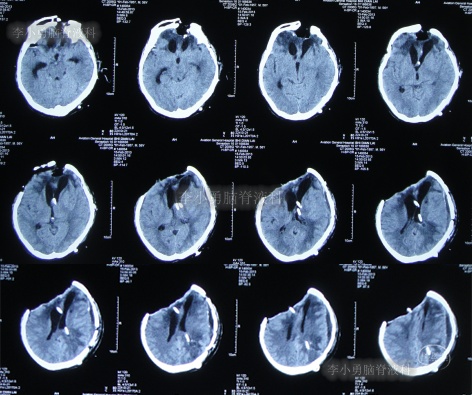

2013年1月17日(入院治疗78天),晚上19点左右,患者突发意识障碍、右侧肢体偏瘫,头部外引流管流出粉红色液体,急查头颅CT示左额颞顶区硬膜下血肿,蛛网膜下腔出血(图-12)。于当晚急诊全麻下进行“左额颞顶硬膜下血肿清除术”。

图-12:2013年1月17日头颅CT

术后患者仍处于昏迷状态;次日2013年1月18日晨起,颅骨缺损处张力较高,复查头颅CT示术区无明显再出血,左顶叶硬膜外血肿,术区脑组织肿胀(图-13),当天进行了左额颞顶硬膜下血肿清除术后,左顶叶硬膜外血肿(图-14)。

图-13:2013年1月18日头颅CT

图-14:2013年1月18日术后头颅CT

2013年1月22日(入院治疗83天),患者术区引流管引流液极少,复查头颅CT脑室较前稍有扩张,右侧骨窗张力仍较高(图-15),进行了侧脑室外引流术(右)+左额颞顶硬膜下引流管去除术+左顶硬膜外引流管去除术。

图-15:2013年1月22日头颅CT

2013年1月25日(入院治疗86天),查头颅CT示脑室有缩小(图-16)。

图-16:2013年1月25日头颅CT

2013年1月31日(入院治疗92天),查头颅CT示脑室进一步缩小,骨窗塌陷(图-18)。

图-18:2013年1月31日头颅CT